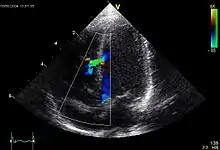

![]() Echokardiogramm eines VSD. |